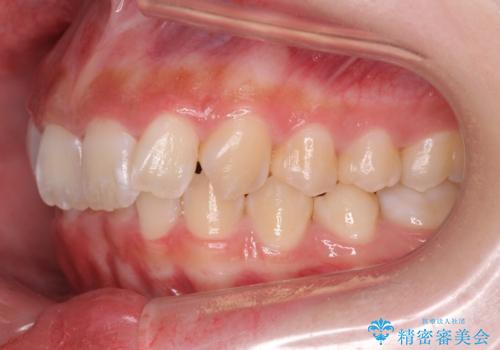

前歯の並び インビザライン 非抜歯で 深いかみ合わせの治療

- 前歯の並びを気にして来院。

上の前歯が内側に倒れこんでいました。

インビザラインで前歯の並びを整えています。

前歯の重なりが大きいいわゆる過蓋咬合を呈していましたが、ある程度適正な重なりにすることができました。